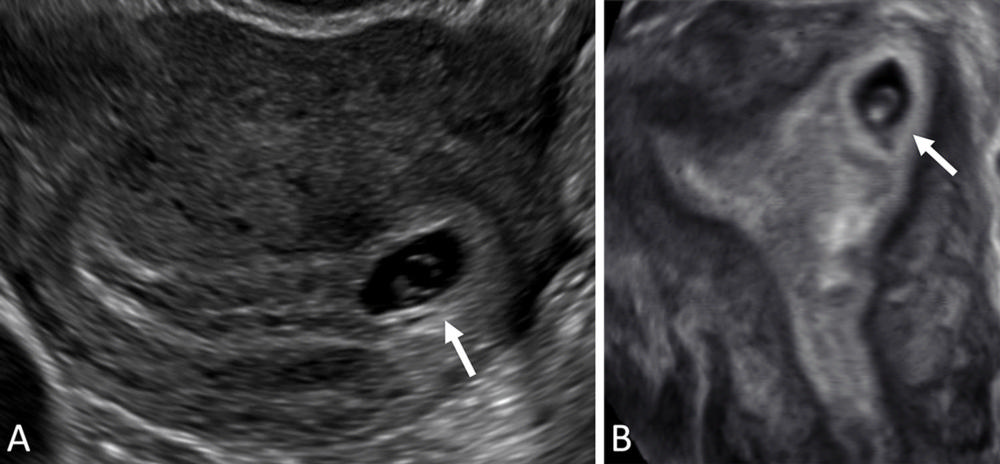

Figure 10. Interstitial ectopic pregnancy (EP). (A) Transvaginal transverse grayscale and (B) coronal reformatted three-dimensional US image in a 29-year-old pregnant patient shows a gestational sac (GS) (calipers) at 5 weeks 3 days. There is intervening myometrium (solid arrow) between the GS and endometrium (*). A claw sign (dotted arrows) of myometrial tissue confirms the pregnancy is implanted in the interstitial (intramyometrial) segment of the tube, termed an interstitial EP. The term ‘cornual EP’ should be avoided. Coronal reformatted three-dimensional US may better demonstrate an interstitial EP separate from the endometrium, as in this case. Diam = diameter.

High-res (TIF) version